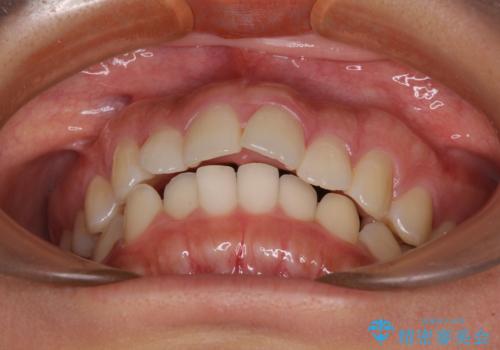

飛び出した上顎前歯 インビザラインで引っ込める

- 前歯の突出感を気にして来院された患者様です。

奥歯の咬み合わせは理想的な咬合に近く、インビザラインでも十分に対応できる歯列でした。

舌の突出癖を改善するためのトレーニングを行いつつ、上下歯列全体を後方に移動させ、更にはIPR(歯と歯の間を削る)によりスペースを獲得することで、口元の突出感を改善することとしました。